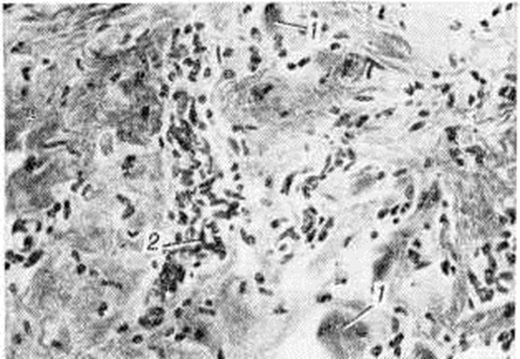

С последней особенностью связывают длительную компенсацию двигательных нарушений у таких больных. В далеко зашедшей стадии Миопатия определяются небольшие островки из атрофированных мышечных волокон на фоне резкого склероза и липоматоза эндои перимизия (рисунок 2), при этом гистологически не представляется возможным дифференцировать Миопатия с нейромышечной атрофией. У пробандов при биопсии мышц находят единичные атрофированные мышечные волокна преимущественно I типа, пролиферацию ядер с переходом их в центр волокна и незначительное увеличение соединительной ткани в эндомизии.